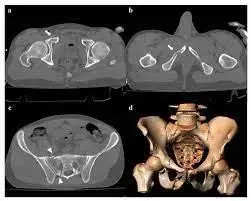

شكل 1: صورة شعاعية أمامية خلفية للحوض تظهر تباعداً كبيراً في الارتفاق العاني، وتوسعاً في المفصل العجزي الحرقفي الأيمن، وتفتتاً في الجناح العجزي الأيمن، مما يدل على إصابة غير مستقرة في حلقة الحوض. -

التصوير المقطعي المحوسب (CT Scan):

- الأشعة المقطعية للحوض مع إعادة بناء ثلاثية الأبعاد (3D Reconstructions): تُعد حاسمة بمجرد استقرار حالة المريض. توفر صوراً تفصيلية للكسور، وتمزقات الأربطة، ومدى الإزاحة. في حالتنا، أكدت الأشعة المقطعية نمط إصابة الضغط الأمامي الخلفي من النوع الثالث (APC III)، مع تباعد الارتفاق العاني بأكثر من 3 سم، وتمزق كامل للأربطة الأمامية والخلفية للمفصل العجزي الحرقفي الأيمن، وكسر العجز من النوع Denis Zone II مع إزاحة كبيرة وتأثر الأعصاب العجزية.

- تصوير الأوعية المقطعي (CT Angiogram - CTA): يُجرى للكشف عن أي نزيف نشط من الأوعية الدموية داخل الحوض، مما يساعد في تحديد الحاجة إلى التدخل الوعائي (مثل القسطرة والانسداد).

- تصوير المثانة المقطعي (CT Cystogram): يُجرى عند الاشتباه في إصابة المثانة، حيث يتم حقن مادة تباين في المثانة للكشف عن أي تسرب. في حالتنا، كشف عن تمزق خارج الصفاق في المثانة.